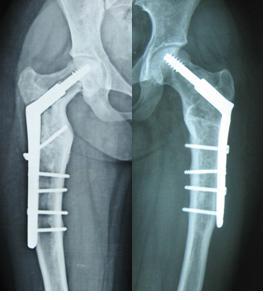

图6 女性,21岁,双侧DF 图7 术后5年力线正常,截骨愈合好